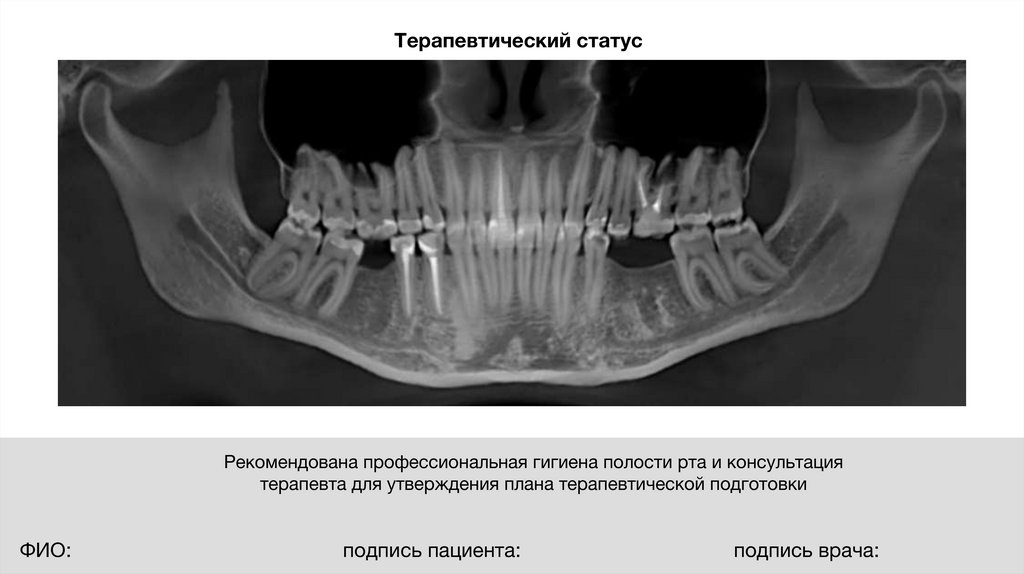

Терапевтический статус

Рекомендована профессиональная гигиена полости рта и консультация

терапевта для утверждения плана терапевтической подготовки

ФИО:

подпись пациента:

подпись врача: